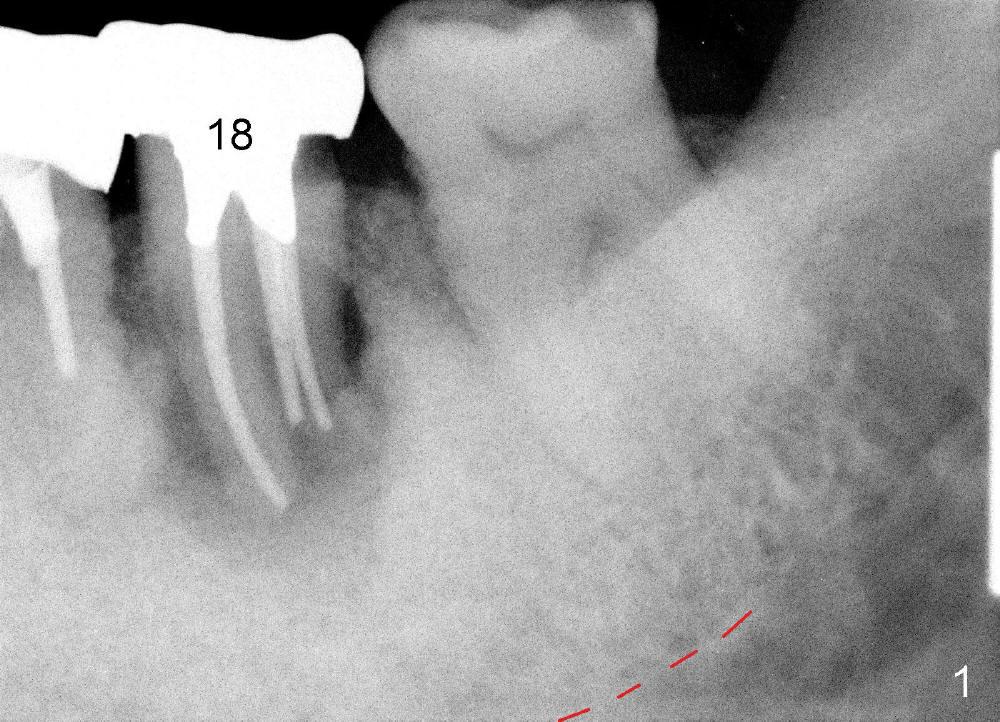

A 84-year-old man has severe pain distal to #18 (Fig.1). The affected tooth is planned to be restored by a 7x17 mm implant (Fig.2).